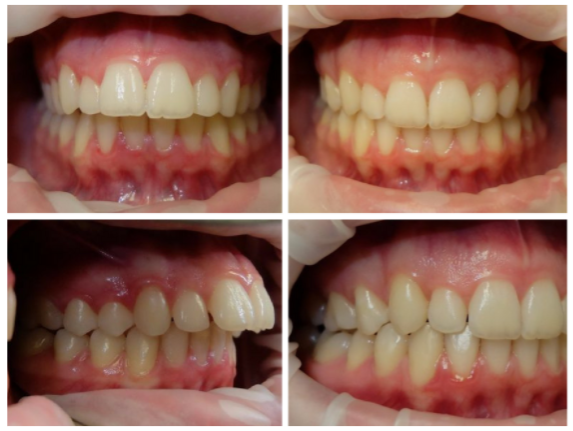

这个弟弟虎牙非常的调皮,下牙也歪。这个case没有拔牙,因为上下差不大,总共是59个牙套,时长18个月。